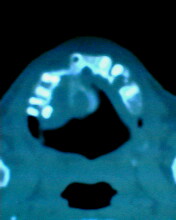

患者:男71岁,右侧上颚肿物无痛性生长7年.

右上颌骨近中线部见类圆形低密度区,上方见一液平,周围见一薄硬化环,前下方见一牙根,后方累及水平板。上方突入鼻腔前下部,下方突入口腔。

考虑:右侧上颌骨囊肿伴感染。